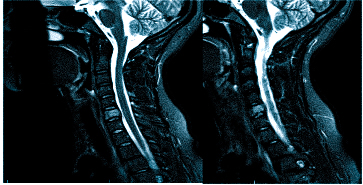

- МРТ (магнитно-резонансная томография) — процедура, которая предоставляет полное представление о состоянии исследуемой области и о наличии заболеваний. Снимки получаются благодаря воздействию магнитного поля на организм.

МРТ при головных болях (в трех проекциях) позволяет получить объемные изображения, что помогает выявить даже незначительные изменения и отличить патологию от нормы.

Причин головной боли множество, и не всегда их можно определить без современных методов визуализации. Цефалгию могут вызывать повышенное внутричерепное давление, сосудистые мальформации, опухоли и посттравматические осложнения. Выбор между МРТ и КТ зависит от предполагаемой патологии. Оба метода взаимодополняют друг друга, но решение о том, что лучше в конкретном случае, принимает врач, учитывая жалобы, показания и противопоказания. МРТ и КТ с контрастом дают сопоставимые по качеству снимки, но используют разные принципы построения изображений. Чем раньше будет установлена причина и начато лечение, тем выше шансы на полное выздоровление.

Существует несколько видов магнитно-резонансной томографии головы: нативная, с контрастным усилением и ангиорежим. Ответить на вопрос: “Какую МРТ делать при головной боли?” не всегда просто, так как выбор зависит от клинической картины.

Для оценки опухолевых новообразований и определения стадийности, включая метастатическое распространение, используется МРТ с контрастированием. Препараты на основе хелатов гадолиния помогают выявить даже небольшие опухоли в труднодоступных местах. Поэтому магнитное сканирование с усилением эффективно, если другие методы визуализации дали неоднозначные результаты. При подозрении на сосудистое заболевание головного мозга лучше проводить сканирование в ангиорежиме.